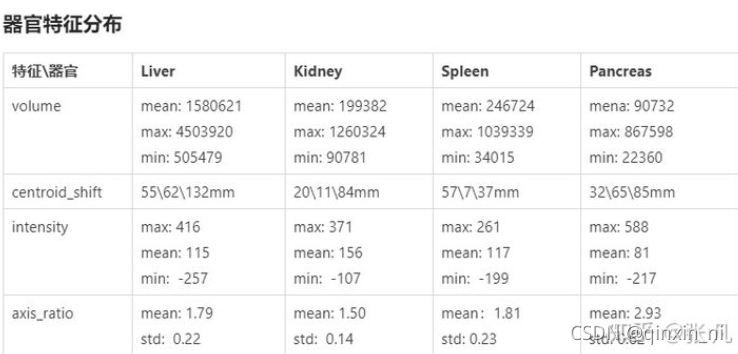

各个器官形状特征的分布如下。参考器官volume特征,设置保留最大连通区域的阈值;参考intensity特征,设置对比度增强参数;参考centroid_shift特征,统计器官之间的相对位置关系;参考axis_ratio特征,统计器官的形状差异。不同器官的大小符合正态分布;不同器官的相对位置是固定的;胰腺的形状差异较大。